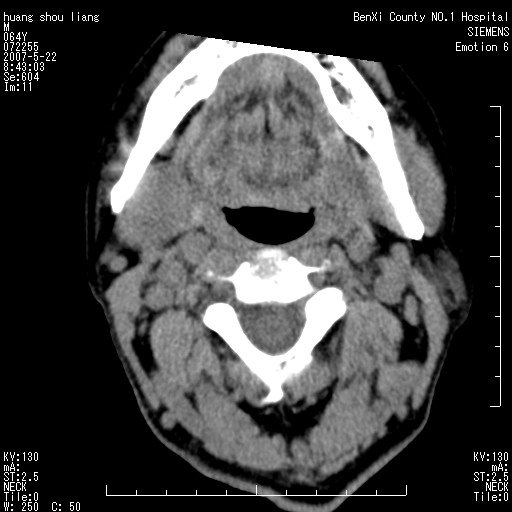

男性,64岁。颈部包块8年。最近增大。

对不起大家,可能是片子发太多有点乱,正常腮腺在下颌角的外侧,颌下腺在下颌体的中部内侧,本例在下颌角内侧偏下,和腺体一点关系都没有,从vrt和mpr上可以很明显看出来,再者肿块是好多粘连在一块的,大家在仔细看看,左侧可能也是吧,我还是考虑为肿大的淋巴结融合在一块,但性质??????

右侧腮腺下部均匀软组织密度肿块,外形不规则,与周围组织分界清晰,考虑右侧腮腺混合瘤或多形性腺瘤。

多考虑颌下腺混合瘤恶变,建议进一步检查,另外楼主重建图像很漂亮。

大家好,病理结果出来了,如大家所说,颌下腺混合瘤。

唉,解剖没学好吧,我诊断错了,不过还是有些不理解回去我在多看看书,谢谢大家的参与,以后我还会奉献好的病例。